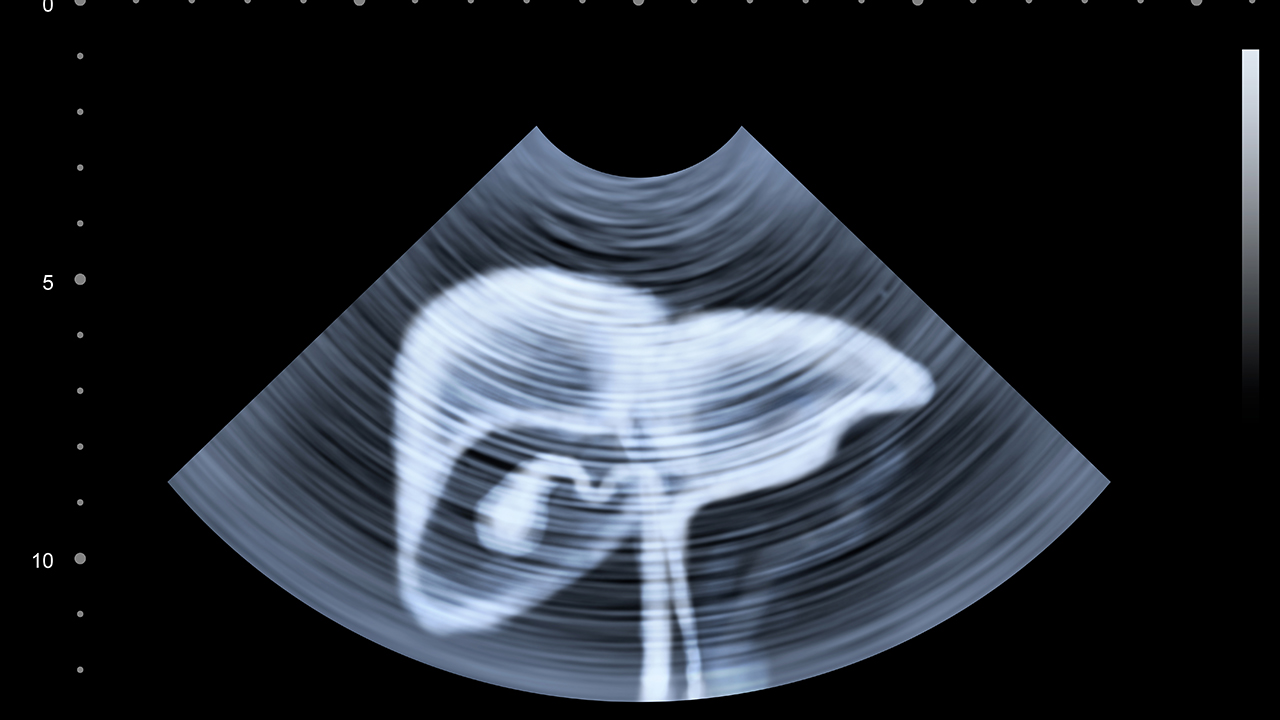

肝癌的预防与健康管理至关重要。对于高危人群,如慢性肝炎患者、肝硬化患者等,应定期进行肝脏超声和甲胎蛋白检查。日常生活中应避免饮酒、注意饮食卫生、避免食用霉变食物。保持良好的生活习惯,适当运动,增强免疫力。对于已确诊的肝癌患者,应积极配合治疗,定期复查,保持良好的心态。肝癌的治疗需要多学科协作,患者应选择正规医院就诊,接受规范治疗。